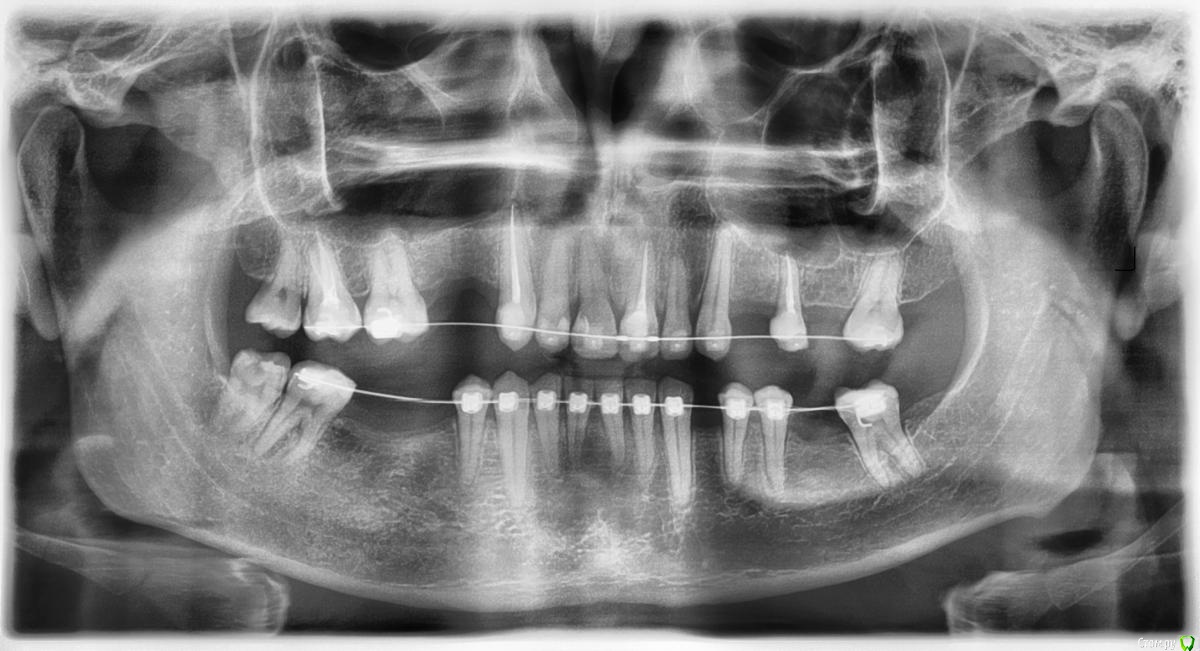

В данный момент прохожу ортодонтическое лечение для последующей имплантации и исправлений прикуса.

По собственной инициативе посетил пароднтолога. Результаты - диагноз "хронический генерализированный пародонтит легкой степени.

Прогноз у доктора, по её словам, благоприятный при ежегодном рентген-контроле и жестком соблюдении гигиены полости рта  с периодической глубокой чисткой.

ОТПГ прикладываю.